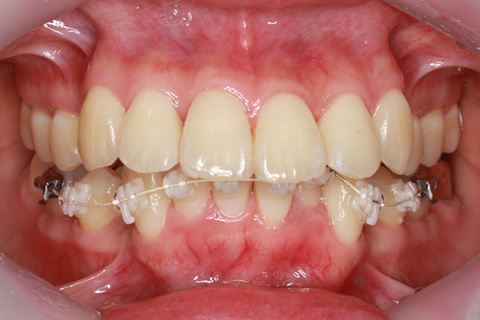

フルリンガル矯正2:上下の歯を舌側矯正で治療(矯正期間18ヶ月)

- 年齢・性別

- 42歳男性

- 治療期間

- 1年6ヶ月

- 抜歯

- なし

- 治療費

- 120万円(税込み)

- 備考

- マルチブラケットを用いた矯正治療

- 治療内容

- 反対咬合をフルリンガル矯正治療にて改善

- 施術の副作用(リスク)

- 表側矯正と比較して、歯根の角度を確立する「トルク」の力がかかりにくい。